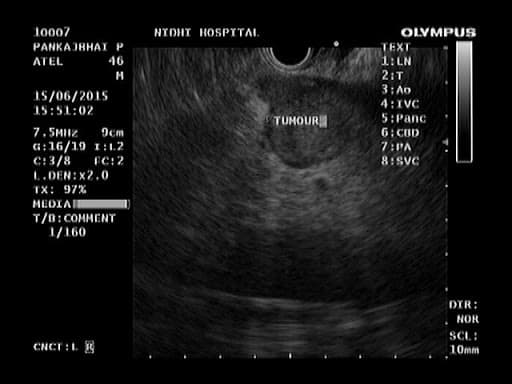

A flexible endoscope which has a small ultrasound device built into to end can be used to see the lining of the esophagus, stomach, small bowel, or colon. The ultrasound component produces sound waves that create visual images of the digestive tract which extend beyond the inner surface lining. Endoscopic ultrasound examinations (also called endoluminal endosonography) may be performed through the mouth or through the anus. EUS is performed under sedation.

EUS provides more detailed pictures of the digestive tract anatomy EUS can be used to evaluate an abnormality below the surface such as a growth that was detected at a prior endoscopy or by X-ray. EUS, because of its ability to examine through the layers of the surface of the GI tract, provides a detailed picture of the growth, which can help the doctor determine its nature and decide on the best treatment.

EUS can also be used to diagnose diseases of the pancreas, bile duct, and gallbladder when other tests are inconclusive, and EUS can be used to determine stage of cancers. Tissue samples can be obtained and certain therapies (such as the removal of certain cysts or aspiration of lymph nodes) can be performed with EUS guidance.